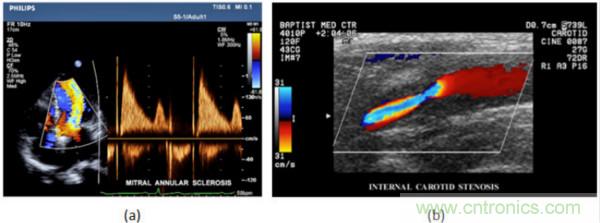

在CW和PW多普勒模式中,流信息是從一個聚焦聲束中獲得的,類似于A模式成像。在20世紀80年代,研究人員基于彩色多普勒技術(shù)完成了血流分布的二維信息可視化。彩色多普勒處理也是基于B模式/PW模式信號路徑。從感興趣區(qū)域收集多幀RF數(shù)據(jù)。由于感興趣區(qū)域中的血液流動導致圖像幀之間存在數(shù)據(jù)差異。相域中的自相關和時域中的互相關兩種算法可從RF數(shù)據(jù)中提取數(shù)據(jù)方差(即血流速度和方向信息):。根據(jù)預定義的顏色漸變條相應地映射包括速度和方向的血流信息。通常,藍色和紅色代碼分別識別朝向和遠離換能器移動的血流。當流速增加時使用更亮的顏色,反之亦然。顏色映射的2D分布始終疊加在B模式圖像上,以實時同時顯示個體解剖結(jié)構(gòu)和血流。它對于診斷心血管疾病,如血管閉塞和心臟瓣膜反流,極其有用。典型的彩色多普勒圖像如下圖所示,(b)顯示頸動脈狹窄引起的血流流速變化。

圖7.彩色多普勒成像:(a)以彩色多普勒和CW模式獲得的圖像(由Philips提供); (b)顯示頸動脈狹窄的彩色多普勒(由GE提供)